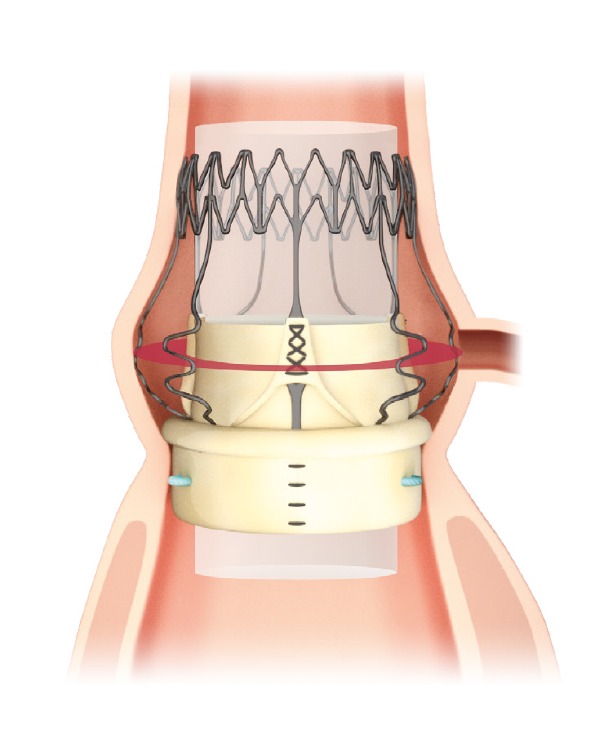

Designed for the future: the ideal docking station for Valve-in-Valve

Perceval Plus is a valve designed for the future. Not only is it durable,9 but it also gives patients even broader treatment options for their future. Its exclusive stent design allows even circumferential expansion to accommodate future transcatheter valves, making Perceval Plus ViV friendly by design. Thanks to its unique features, all patients eligible for biological AVR may benefit from a Perceval Plus implant.**12,13

The Nitinol stent provides clear visibility under fluoroscopy and CT scan to identify landmarks which facilitate the ViV procedure.

Even circumferential expansion

The inflow ring can be evenly and circumferentially expanded up to 2.5mm above its nominal size, which allows for hemodynamic advantages and greater compatibility with TAVI models and sizes.

Minimized risk of coronary obstruction

Perceval Plus leaflets remain open when a TAVI is deployed inside it. The sinusoidal struts and the open leaflets create a space between the coronary ostia and the leaflets themselves wich is preserved even after the TAVI deployment.

Minimized risk of sinus sequestration

By design, the Perceval Plus leaflets, when open, do not touch the STJ, thus avoiding sinus sequestration.

Designed for MICS

Perceval Plus RelyON System and Minimally Invasive Cardiac Surgery were made for each other thanks to the sutureless design of the valve and the length and diameter of the new Deliver System. The System allows for minimized incision,11,15 maximized visibility11,12, faster learning curve14,15 and a reduced manipulation of the aortic root.11,15,16

Minimized incision11,12

Thanks to the unique collapsible profile and sutureless design of the valve and the design of the Delivery System, Perceval Plus RelyON System allows a reduced incision size and less surgical trauma.2,11,17

Maximized visibility during implantation11,12

The collapsible profile of the valve and the small diameter of the Delivery System allow the surgeon full visibility of the annulus and of the anatomical structures during implantation and deployment for great confidence and fast, precise positioning at the implantation site.2,8